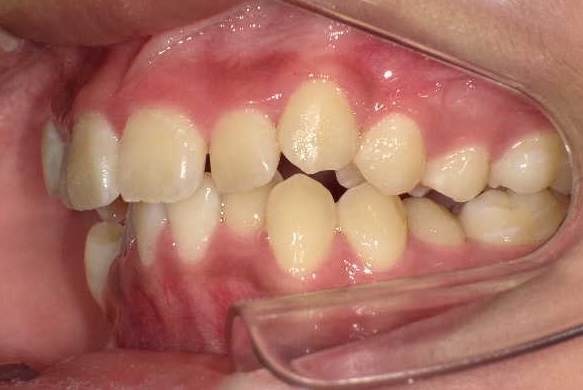

症例1-③

そこで当院では、ここからは、当院の成人非抜歯の技術を用いて、永久歯を抜くことなく(親知らずは除く)治療をゴールまでもって行きます。

症例1-③の写真が完成時の所見です。いかがでしょう、口もとも美しくきれいな永久歯列の完成です。